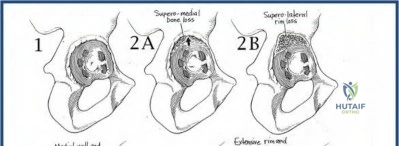

A 72-year-old female is undergoing revision total hip arthroplasty for aseptic loosening. Intraoperative assessment of the acetabulum reveals superior migration of the cup of 3.5 cm, medial migration past the Kohler line, and an ischiolytic lesion. There is severe superior bone loss with less than 40% host bone contact available for the new component, but the anterior and posterior columns remain intact. What is the most appropriate acetabular reconstruction strategy?

In a revision THA setting, a patient presents with massive acetabular osteolysis. Preoperative radiographs reveal a distinct transverse fracture line through the acetabular fossa and medial translation of the inferior hemipelvis relative to the superior hemipelvis. What is the diagnosis, and what is the most appropriate intraoperative implant consideration?

A 72-year-old male presents with a loose acetabular component. Imaging demonstrates an inferiorly migrated teardrop, a fracture line extending through the posterior column, and complete separation between the superior and inferior halves of the hemipelvis.

During preoperative planning for a revision total hip arthroplasty, you classify the acetabular defect as a Paprosky Type IIIB. Which of the following radiographic findings characterizes this specific defect?